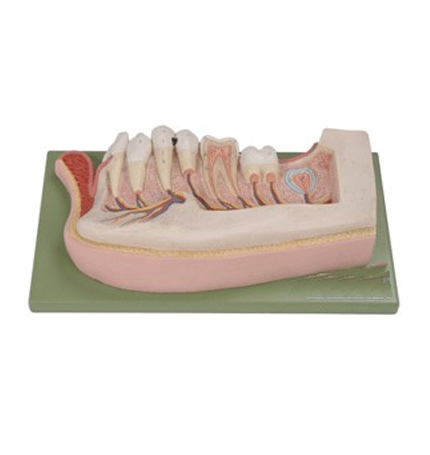

��ǻ���� TEETH